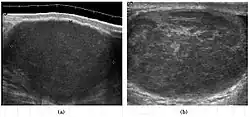

Teratoma Although teratoma is the second most common testicular tumor in children, it affects all age groups. Mature teratoma in children is often benign, but teratoma in adults, regardless of age, should be considered malignant. Teratomas are composed of all three germ cell layers, i.e. endoderm, mesoderm and ectoderm. At ultrasound, teratomas generally form well-circumscribed complex masses. Echogenic foci representing calcification, cartilage, immature bone and fibrosis are commonly seen [Fig. 5]. Cysts are also a common feature and depending on the contents of the cysts i.e. serous, mucoid or keratinous fluid, it may present as anechoic or complex structure [Fig. 6].

Fig. 5. Teratoma. A plaque-like calcification with acoustic shadow is seen in the testis. -

Fig. 6. Mature cystic teratoma. (a) Composite Image. Mature cystic teratoma in a 29-year-old man. Longitudinal sonography image of the right testis shows a multilocular cystic mass. (b) Mature cystic teratoma in a 6-year-old boy. Longitudinal sonography of the right testis shows a cystic mass containing calcification with no obvious acoustic shadow.